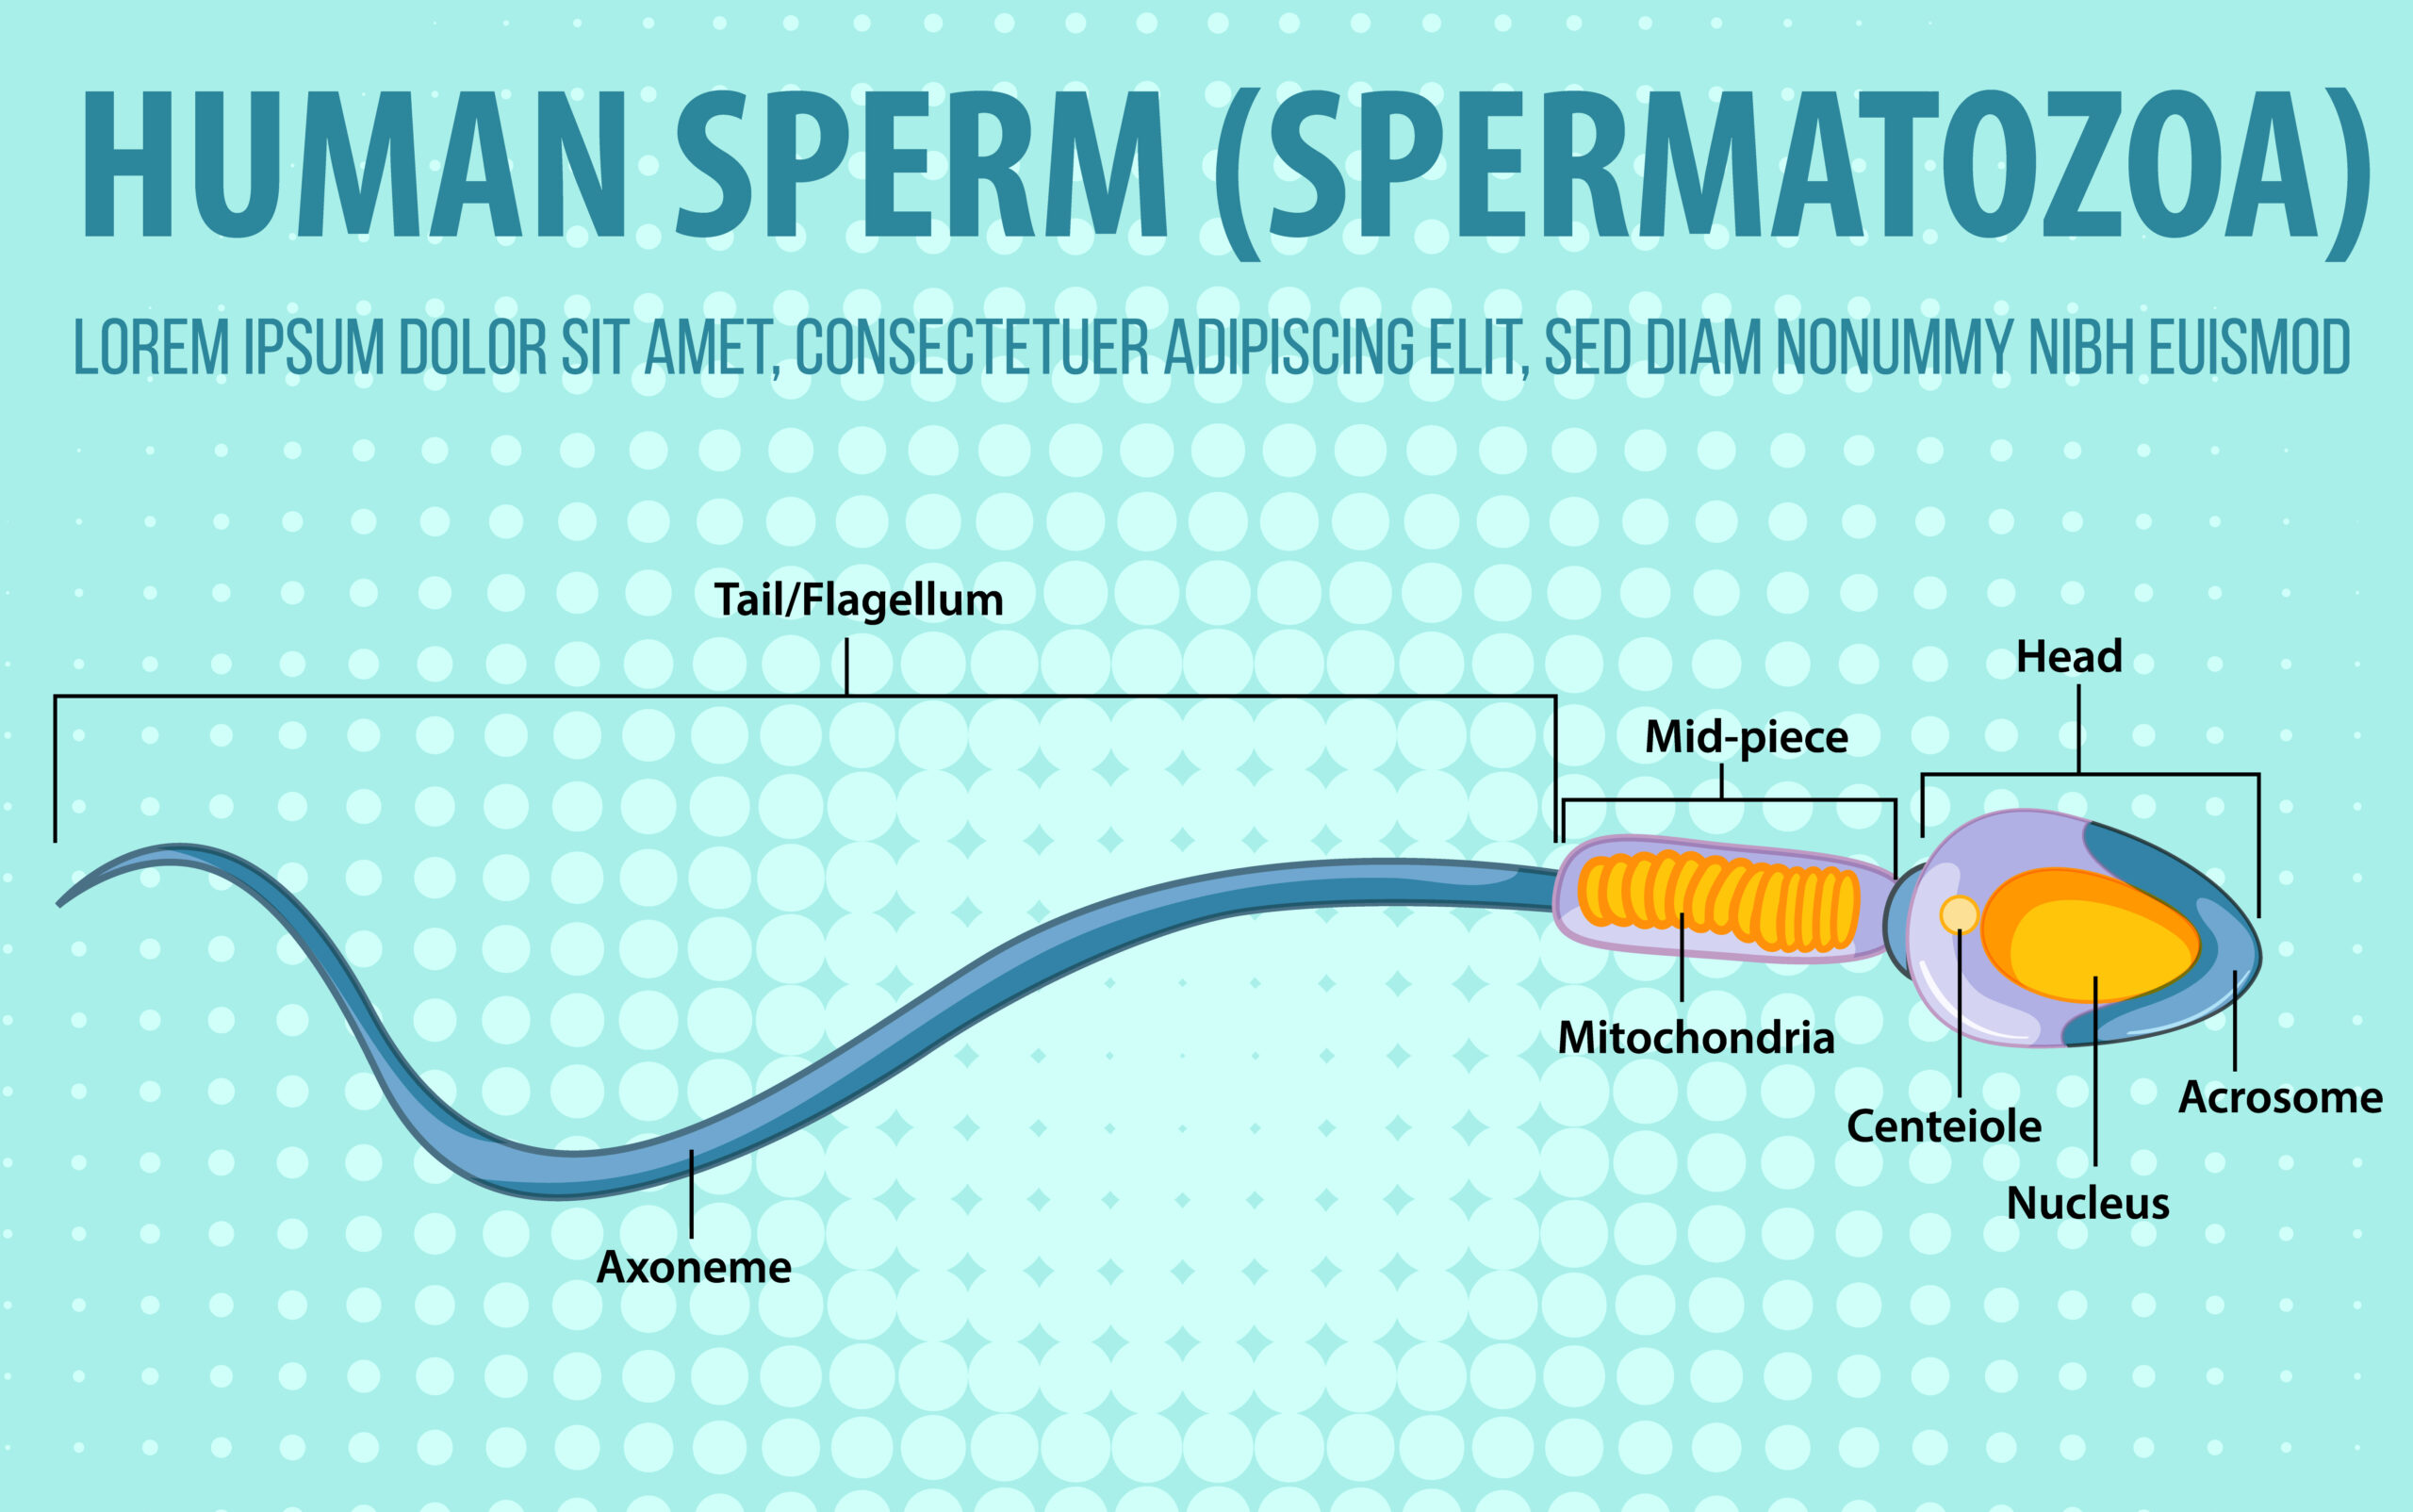

האם הניתוח משפיע על התפקוד המיני?

בחלק מהמקרים (גם בטיפול התרופתי) תיתכן שפיכה אחורית (שפיכה לשלפוחית) – תופעה לא מזיקה, שאינה פוגמת בתחושת ההנאה, אך רלוונטית למי שמתכנן פוריות.